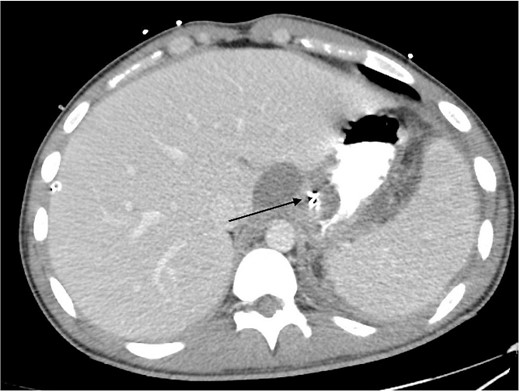

Total Parenteral Nutrition (TPN) was commenced immediately post-operatively. His post-operative course was complicated with fevers, necessitating a CT abdomen pelvis on Day 5, which demonstrated ileus with no other complications, such as ongoing leak. The endoscopic clips are noted on this CT in Fig. 4. Indeed, NG feeds were commenced on post-operative Day 7, following ongoing high NG outputs necessitating 2-hourly aspirates. TPN was ceased on Day 13, and he was discharged on Day 14 with oral antibiotics, a thickened fluid diet, and an NGT. On follow up, his NGT was removed, and he was upgraded to a full diet.

Intravenous and oral contrast enhanced CT abdomen/pelvis on post-operative Day 5, in axial view, demonstrating the placement of haemostatic clips at the previous site of perforation (arrow), with no evidence of ongoing leak.